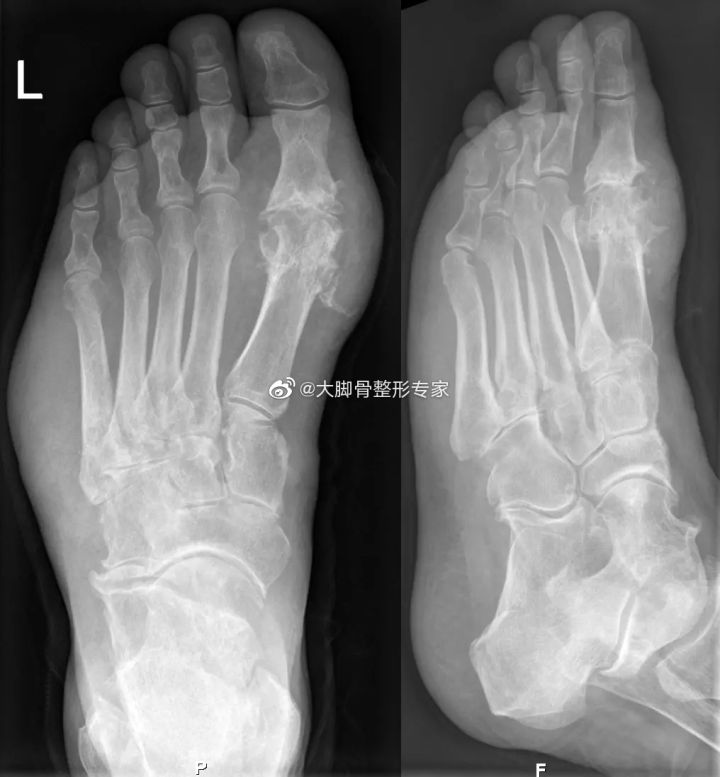

拇外翻X光:第一跖骨向内侧偏斜,第一趾骨向外侧偏斜,两者形成犄角

痛风X光,侵蚀第一跖趾关节及骨头

除外上述症状 ,还有一些实验室等检查,能够有效诊断拇外翻和痛风。X光能有效确诊拇外翻,通过X光能够清晰的看到拇外翻偏斜的角度,第一二跖骨间角度,关节间隙等;X光也能看到痛风石的堆积情况,痛风石会侵蚀骨头,出现在第一跖趾关节周围的痛风石堆积,对第一跖骨头的侵蚀情况也清晰可见。